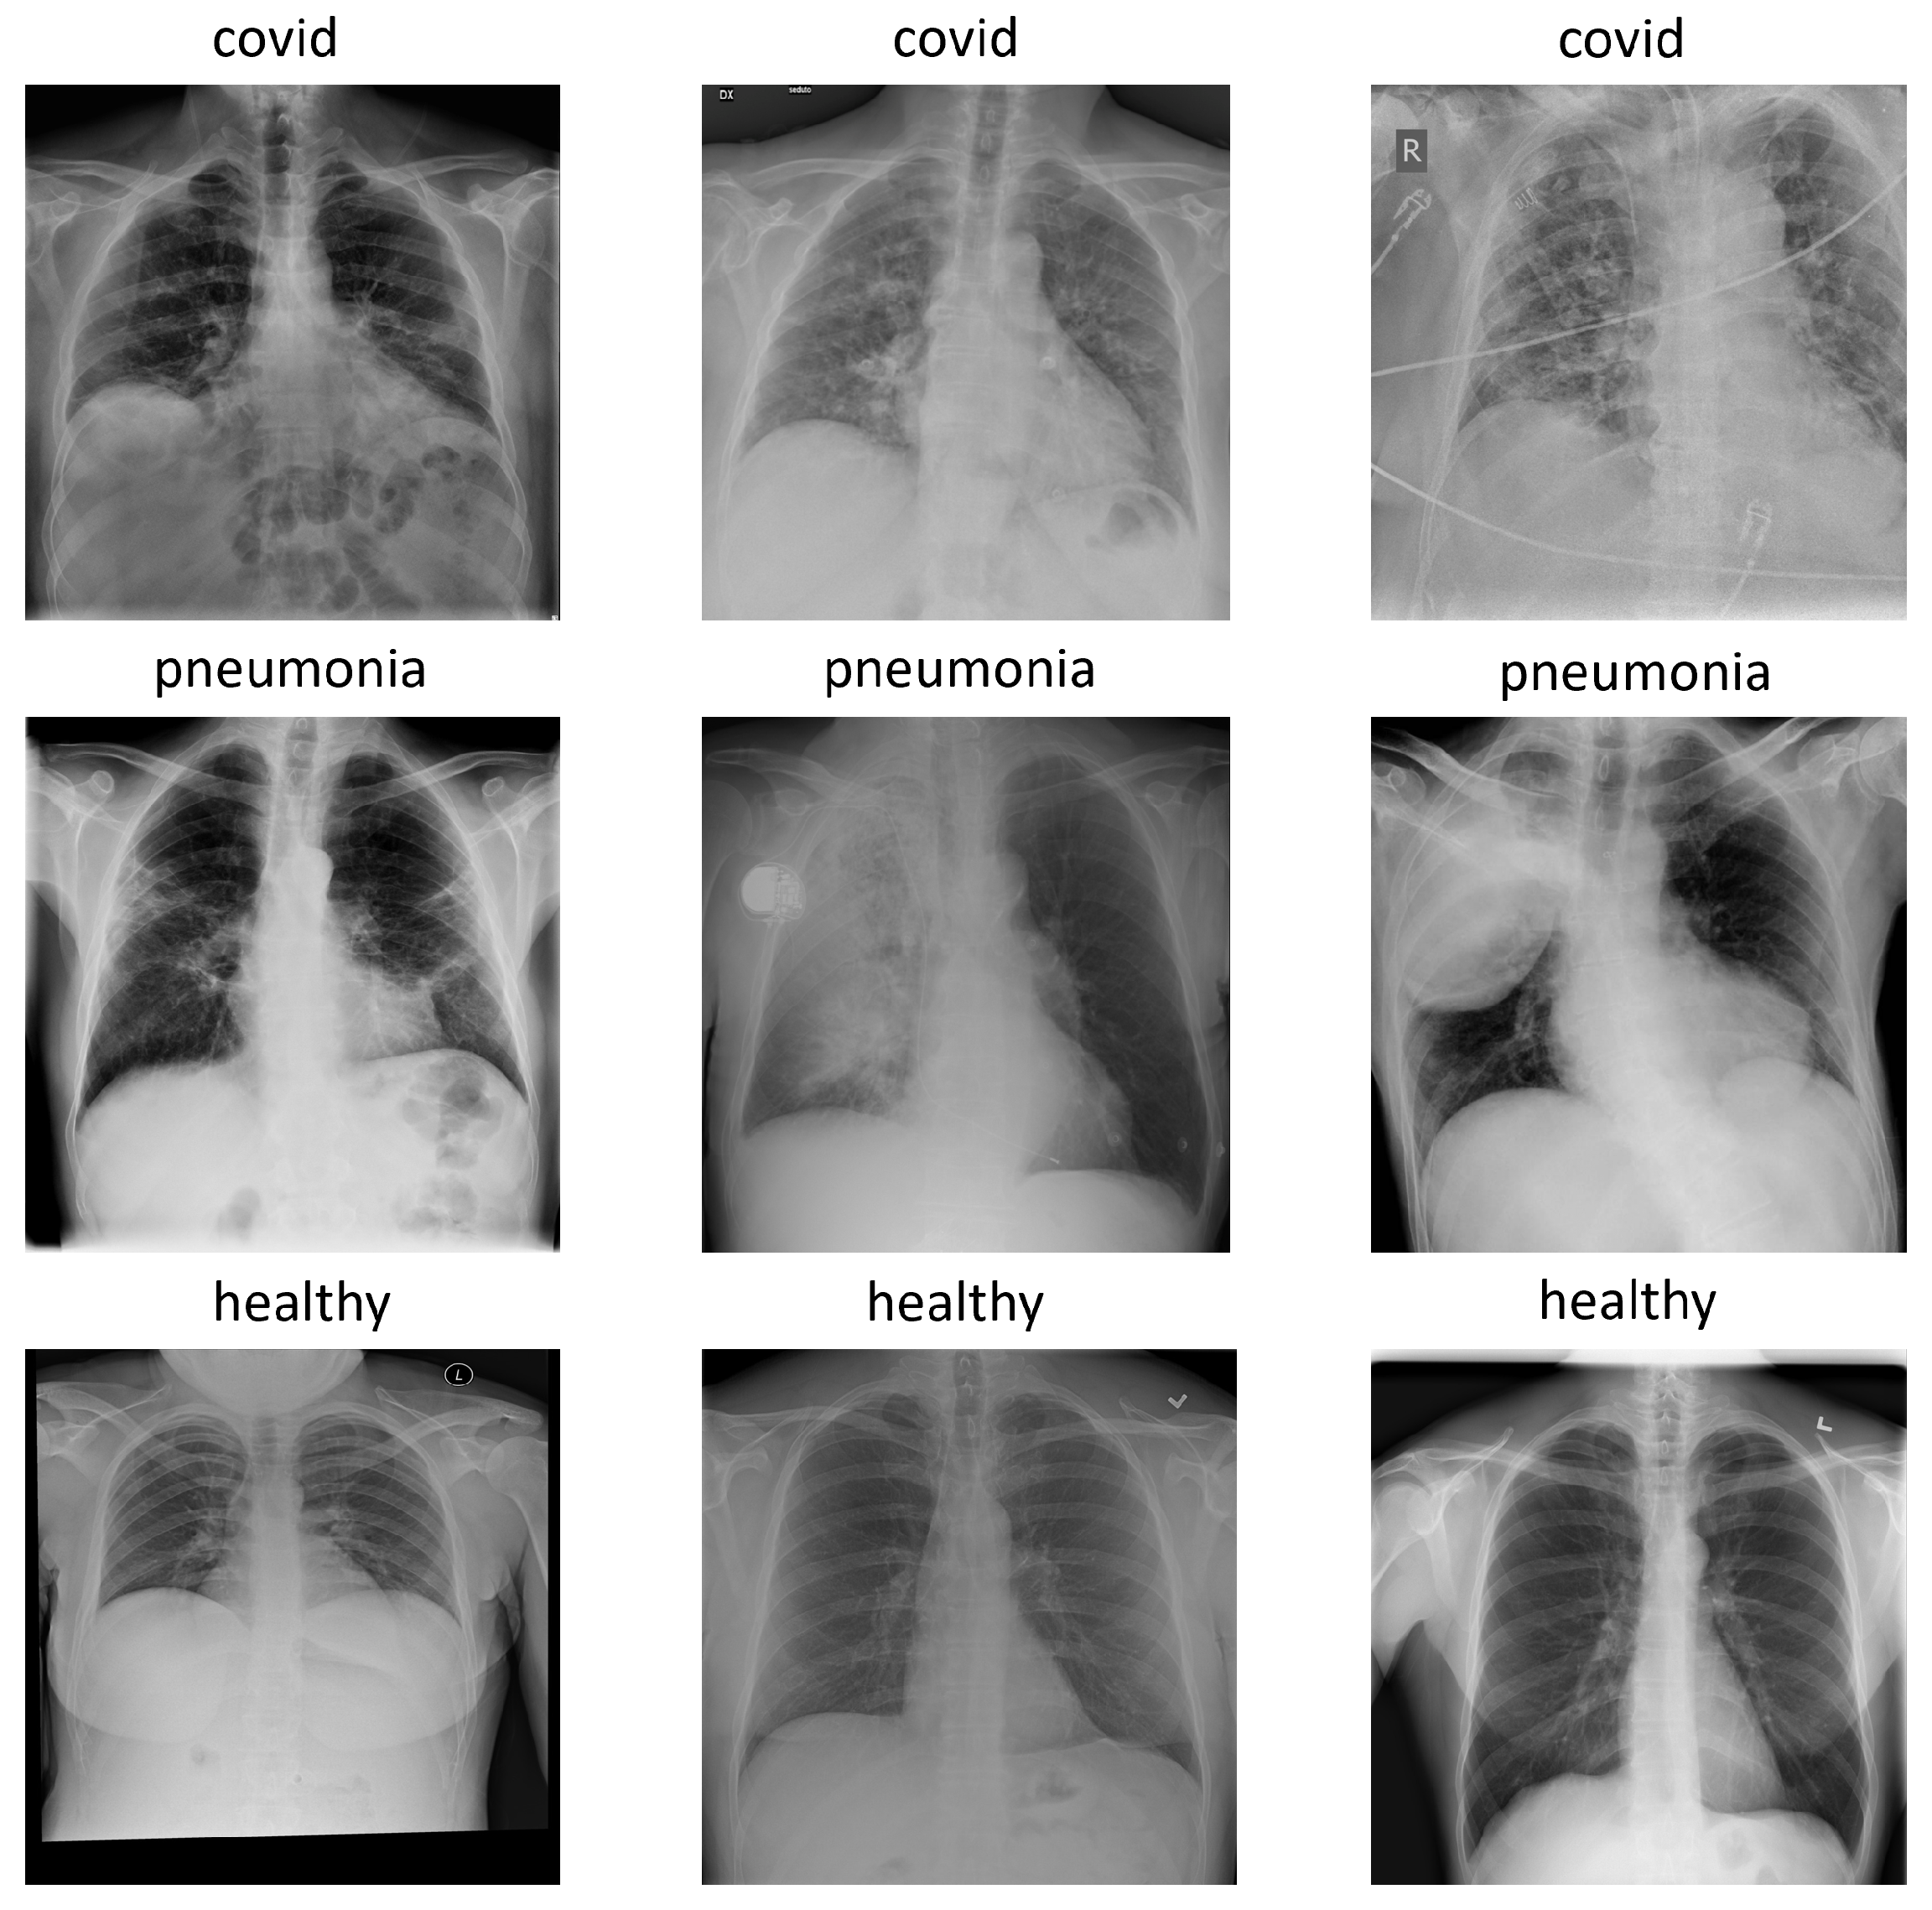

2.1. COVIDx Dataset